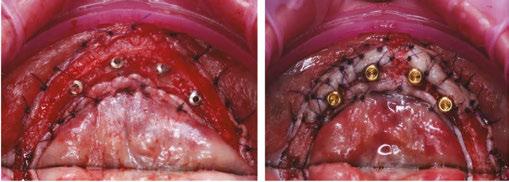

Figures 9A-9I: Management of ANS greenstick fracture via horizontal ridge augmentation. 9A. Pre-op. 9B: Stabilization of ANS greenstick fracture via “sausage”-based technique using two 20x30 RCMs and 4-0 PGCL sutures. Membrane-stabilizing sutures used: periosteal vertical mattress suture (PVMS) at lateral-most extent of the graft area. PVMS at the medial extent of each membrane (another PVMS was added just left of midline after photo was taken). Apical periosteal and palatal membrane tacking sutures. 2.5cc particulate 80/20 FDBA (corticocancellous)/xenograft (porcine) was used. 9C. 6-month post-op. Patient allowed limited wear of denture (shortened flange in anterior) 2 months post-op. 9D. Uncovering with view of the repaired ANS with regenerated bone. Implant placed in NP canal @ 25 Ncm. 9E. Occlusal view. 9F. L-PRF prepared (700 RCF, 8 minutes) and placed all along arch to aid in soft tissue healing. Flaps intentionally sutured to allow healing by secondary intention to increase KT. Conversion prosthesis loaded, patient educated about anterior cantilever. 9G. 1-week follow up. The power of L-PRF. 9H. 3-month follow up. 9I. Uncover at 3 months post placement of NP implant. 9J. CBCT Axial View. AP spread with (14.4 mm) and without (9.3 mm) NP implant